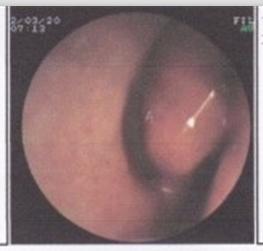

【鼻甲肥大会引起哪些并发症】鼻甲肥大通常都是由于生活中一些常见因素引起的,正是由于其常见常常被很多人忽略,只有等到病症极其严重的时候才会想到去就医,这时候往往病情已经发展的极为严重,这点需要患者朋友及时注意起来。

鼻甲肥大会引起哪些并发症

1、导致鼻塞:由单纯性鼻炎时的间歇性或交替性转变为持续性鼻塞,这是因为鼻粘膜已呈实质性的肥厚,粘膜缺乏收缩功能,所以鼻塞就更严重了。鼻腔持久阻塞,使病人说话带有明显鼻音,好像被捏住鼻子时讲话的声音。

2、嗅觉明显减退:因为鼻呼吸不通,空气中的各种气味,进不了嗅区,也就闻不出味道了。肥厚性鼻炎由于鼻呼吸障碍,鼻甲的后端粘膜往往特别肥厚,它不但阻碍呼吸,并且会影响通向中耳的咽鼓管,使患者发生耳鸣和听力减退。

3、三叉神经痛:肥大的中鼻甲压迫鼻中隔时会出现三叉神经痛,更令人痛苦和烦恼。